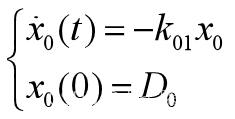

3、口服或肌肉注射

这种给药方式相当于在药物进入中心室以前,先有个将药物吸收入血液的过程,可以简化为一个吸收室,如图15所示,x0(t)是吸收室的药量,药物由吸收室进入中心室的速率为k01。

图15 详细的三房室模型

吸收室药量满足 【4.8】

【4.8】

将【4.8】代入 得到

得到 【4.9】

【4.9】